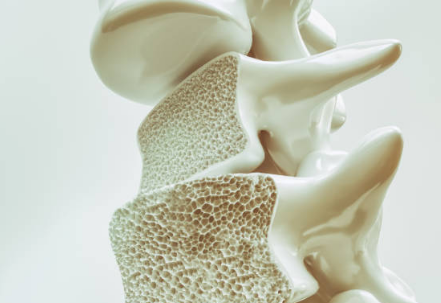

골다공증은 뼈의 밀도가 감소하여 뼈가 약해지고 쉽게 골절될 위험이 커지는 질환입니다. 주로 노화, 영양 부족, 생활습관, 유전적 요인 등 다양한 원인에 의해 발생하며, 초기 증상이 거의 없어 "조용한 질환"이라고 불리기도 합니다. 이로 인해 골다공증은 예방과 조기 관리가 매우 중요한 질환으로 인식되고 있습니다.

골다공증은 뼈의 밀도가 감소하여 더 쉽게 골절이나 골대 손상을 일으킬 수 있는 상태입니다.

골다공증은 골밀도가 저하되어 골이 부드럽고 턆터져서 골절이 쉽게 일어날 수 있는 상태입니다. 정기적인 검진과 건강한 생활습관이 중요합니다.